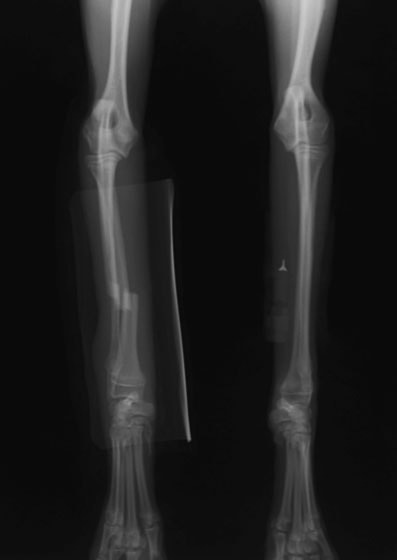

症例3:キルシュナーワイヤーのピンニングによる整復

ペルシャ猫 11ヶ月齢 雄

他院にて左大腿骨遠位の成長板骨折(salter-harrisⅠ型)が認められており、治療相談を目的として来院。当院にて、キルシュナーワイヤーを用いたピンニングにより骨折部位の整復を行いました。術後の経過は良好で、現在も経過観察中です。

術前レントゲン

術後レントゲン